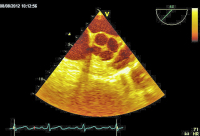

Parasternaler Längsschnitt

Abbildung 1: Parasternaler Längsschnitt: Die Aortenklappe weist zarte Klappentaschen mit einer unbehinderten Öffnungsfunktion auf.